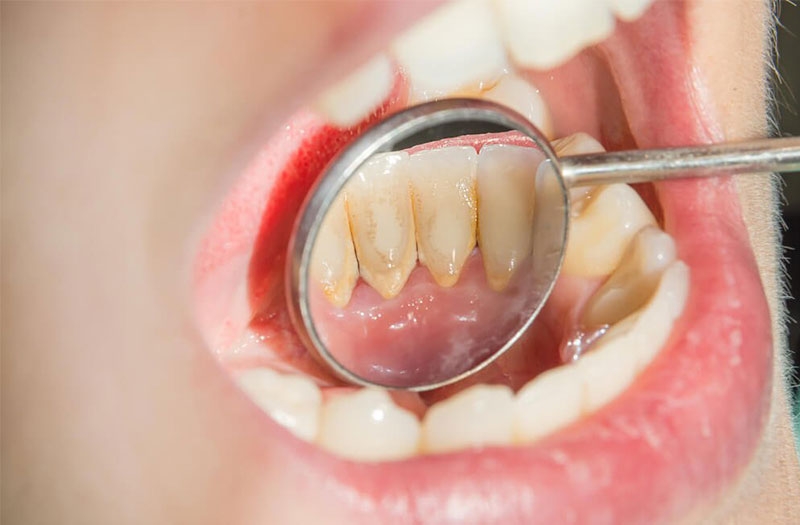

Trước khi tìm hiểu giá cạo vôi răng, cạo vôi răng bao nhiêu tiền thì đầu tiên bạn cần hiểu về vôi răng là gì. Vôi răng là các mảng bám dính chặt trên bề mặt răng. Chúng được tạo nên chủ yếu từ các mẩu vụn thực phẩm còn sót lại trên răng kết hợp cùng với xác vi khuẩn.

Thời gian đầu tích tụ, các mảng bám này thường khá mềm và theo thời gian chúng sẽ ngày càng cứng dần và bị vôi hóa hay cao răng. Vôi răng thường sẽ bám ở kẽ răng, vổ răng, dưới nướu răng của mình.

Vôi răng là các mảng bám dính chặt trên bề mặt răng